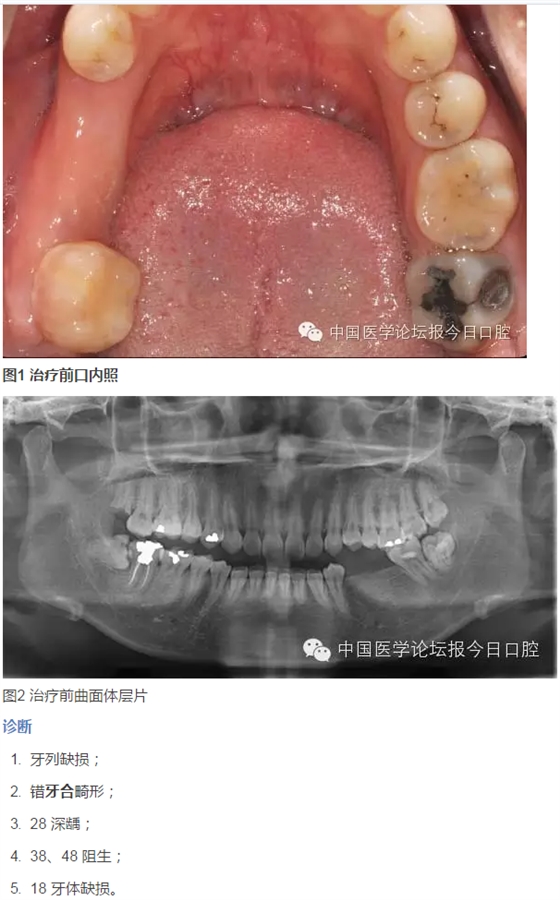

臨床檢查

患者臉型不對稱,右側(cè)大于左側(cè)。

牙周情況尚可,有少量牙結(jié)石,牙齦無明顯紅腫。35、36 缺失,25、26 過長,17 與47,27與37正鎖牙合,咬合時26、27 的牙尖頂?shù)綄︻M缺牙區(qū)牙槽嵴黏膜上。37、47死髓牙。

全口曲面體層片顯示:35、36缺失,缺牙區(qū)牙槽骨有足夠的骨高度,47未行根管治療,38、48近中阻生,18殘根,28頰面深齲近髓。